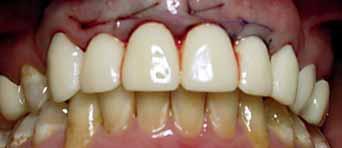

The patient had moderate Class II skeletal pattern with average Frankfort-mandibular planes angle and lower anterior face height. There was no facial asymmetry and the lips were incompetent with the lower lip trapped at rest behind the upper central incisors (Figure 1).

The oral hygiene was fair but needed improvement prior to orthodontic treatment. All teeth from the left permanent second molar to the right have erupted in both the upper and lower arches. The patient had carious lesions in both upper first molars, upper left second molar and lower left first molar. The maxillary arch was spaced with a midline diastema. Furthermore, there was mild lower labial segment crowding (4mm). The incisor relationship was Class II division 1, the overjet was 12 mm whereas the overbite was increased and complete to the palate

and causing trauma to the palatal mucosa. The centrelines were coincident and the buccal segment relationship was 1/2 unit Class II on both sides (Figure 2).